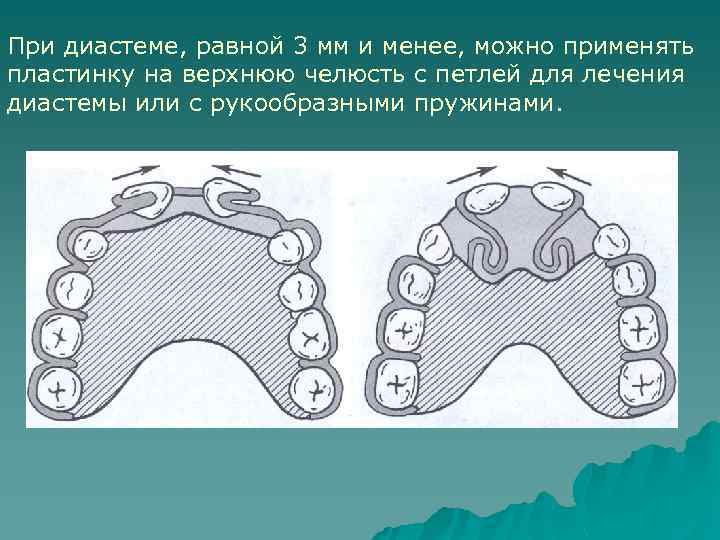

При диастеме, равной 3 мм и менее, можно применять пластинку на верхнюю челюсть с петлей для лечения диастемы или с рукообразными пружинами.